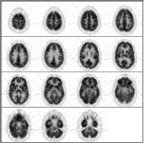

Once again, this is a normal PET scan. We will now learn how to distinguish abnormal from normal brain metabolism.

A convenient way to analyze metabolism in a brain FDG-PET scan is to proceed down a checklist of brain structures. This tutorial teaches such an approach.